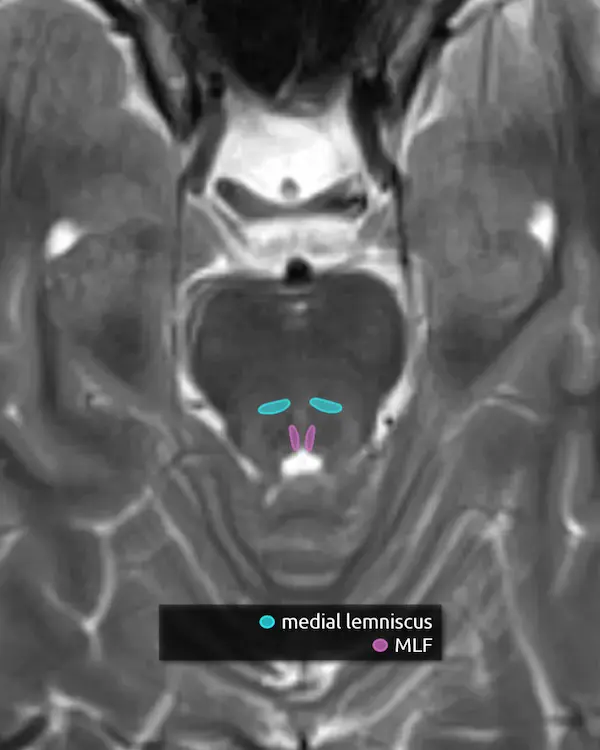

1. Pyramids

2. Inferior cerebellar peduncles

3. Medial lemniscus

4. Medial longitudinal fasciculus (MLF)

5. Inferior olivary nucleus

The inferior olivary nucleus is located in the upper medulla just posterior to the pyramids. It is involved in motor coordination and is a main component of the dentatorubro-olivary pathway (aka the triangle of Guillain and Mollaret), discussed below. A lesion that damages the predominantly inhibitory interneurons in the tracts connecting the corners of the triangle may result in disinhibition of the inferior olivary nucleus, characteristically but rarely manifesting as palatal myoclonus. Over time, the inferior olivary nucleus may swell, become T2 hyperintense, and eventually atrophy, a process called hypertrophic olivary degeneration.

2. Spinocerebellar tracts